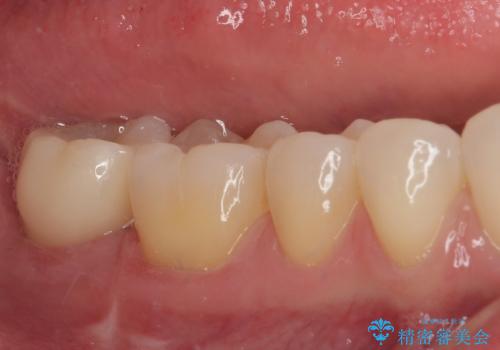

抜歯になった奥歯 速やかな埋入による短期間インプラント治療

- 奥歯が抜歯となり、インプラント治療を希望して来院された患者様です。

来院時には抜歯して1ヶ月ほど経過していたとのことで、3次元レントゲンよりインプラントの早期埋入が可能と診断されました。

インプラント埋入と同時に仮歯を装着するために、事前に仮歯を用意し、速やかにインプラント埋入を行うこととしました。